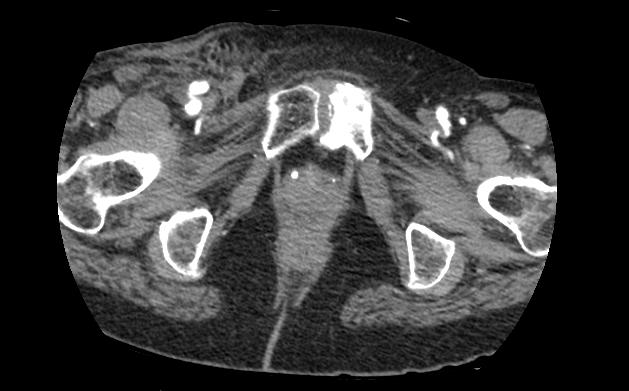

A fistula is a connection between an artery and a vein. A fistula might occur by accident during the arterial puncture, if the needle simultaneously goes into the adjacent femoral vein.

An arterio-venous fistula is diagnosed by using a duplex ultrasound. The following measures are looked for when diagnosing an arterio-venous fistula:

- When visualizing the common femoral artery and vein using color doppler, turbulent blood flow is noticed.

- The blood flow in the artery at the site of the fustula may show reduced velocities, as it heads toward the low resistance vein.

- The blood flow in the vein at the site of the fistula may show arterial characteristics. Following the vein proximally toward the heart shows gradual dampening of the effect.

In both cases of pseudoaneurysm and arterio-venous fistula, visualization should be made carefully from the level of the external iliac vessels and down toward the femoral vessels, as not to miss a finding.